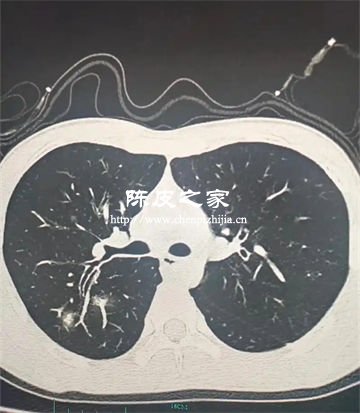

陈皮多糖对PM2.5致肺损伤的防护机制主要体现在抗炎作用、抗氧化应激、抑制气道重塑与纤维化、调节免疫微环境、减少颗粒物沉积与清除等方面。下面进行详细讲解。

PM2.5长期暴露会导致气道杯状细胞增生、黏液高分泌及纤维化,进而引发肺气肿和小气道重塑。陈皮多糖可减少气道黏液分泌,抑制胶原沉积和纤维化进程,缓解PM2.5诱导的气道结构改变。

PM2.5颗粒表面常吸附重金属和有毒物质,沉积于肺泡后难以清除。陈皮多糖主要通过增强黏液纤毛清除功能、结合有毒物质促进颗粒物排出。